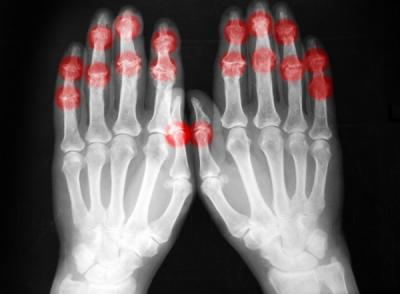

ऑस्टिओआर्थरायटिस जॉइंटमधील हाडांवरील कार्टिलेजचा हा थर कमजोर करतं. त्यामुळे आपल्या जॉइंटचा सरफेस रफ होतो. याकारणाने जॉइंटममध्ये सूज, वेदना आणि ताण निर्माण होतो. पण ही लक्षणे प्रत्येक व्यक्तीत दिसत नाहीत.

'आर्थरायटिस हेल्थ'नुसार, जेव्हा आस्टिओआर्थरायटिसचा विषय येतो तेव्हा याची लक्षणे व्यापक रूपाने वेगवेगळी असू शकतात. जॉइंट हलवताना किंवा मुव्हमेंट होत असताना यातून आवाज येऊ लागतो. हा हाडे एकमेकांना भिडत असल्याचा संकेत आहे. मेडिकलच्या भाषेत याला क्रेपिटस म्हणतात.

पण आर्थरायटिस कोणत्याही इतर लक्षणाशिवाय केवळ लक्षणावरून ओळखला जाऊ शकत नाही. क्रेपिटसशिवाय इतर काही लक्षणे जसे की, जॉइंटमध्ये वेदना ऑस्टिओआर्थरायटिसचं संकेत असू शकतो.